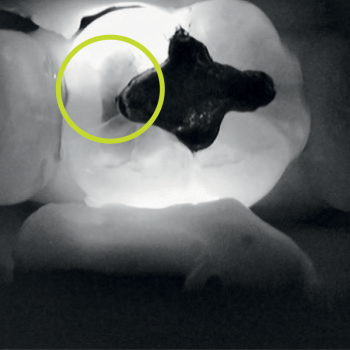

Near-infrared transillumination empowers clinicians to detect proximal lesions that might escape clinical observation and distinguish between lesions confined to the enamel and those that have progressed to the enamel-dentin junction.

Interproximal caries

X-Ray

“It is the best method of caries diagnosis, and you can use it safely. […] [regarding] class II cavities and non-cavitated approximal caries, DIAGNOcam has better sensitivity and specificity than bite-wing x-rays [… ] cavity shape is much better explained and visible.”

— Mikolajczyk M. (2024)